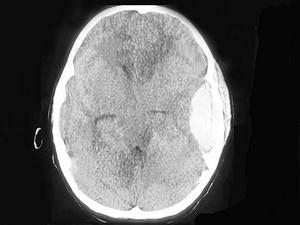

问题 一慢性化脓性中耳炎患者,突发患侧头部剧痛,体温37.5℃,其头颅CT摄片如图,考虑为 ( )

选项 A、硬脑膜外脓肿 B、以上都不是 C、脑脓肿 D、硬脑膜下脓肿 E、化脓性脑膜炎

答案 A